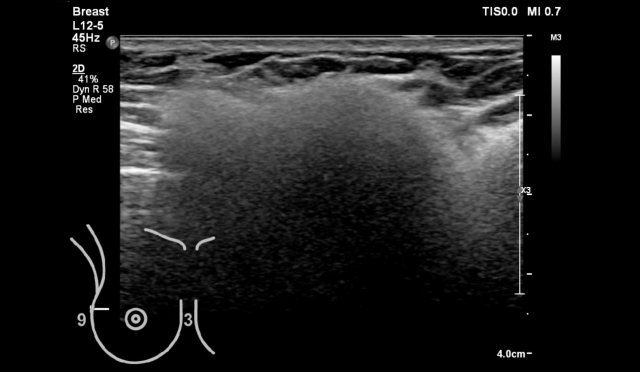

LEFT: no harmonic imaging RIGHT: with harmonic imaging

Harmonics

Harmonic imaging is an ultrasound technique that employs the resonance characteristics of tissue.

It is also calles tissue harmonic imaging or THI.

If you have this possibility on your ultrasound machine, you will notice that images produced with harmonic imaging have a higher resolution and are associated with fewer artifacts than conventional ultrasound imaging.

Posterior shadowing can be enhanced.

Notice that the small breast cancer is better seen with harmonic imaging.

There is a hypoechoic tumor with a hyperechoic halo and a little bit of posterior shadowing. The orientation is vertical.

The border is indistinct and the shape of the tumor is irregular.